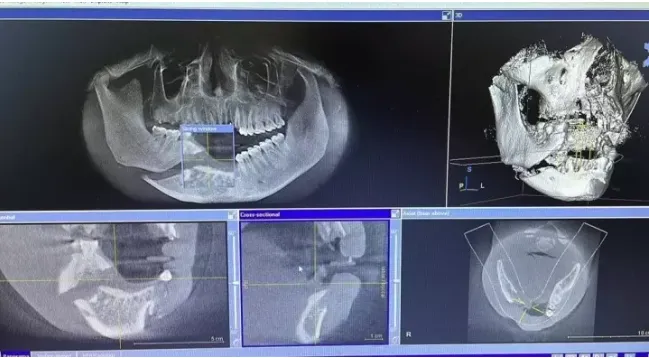

Nam thanh niên 26 tuổi được đưa đến sơ cứu tại một cơ sở y tế trước khi đến Bệnh viện Hữu nghị Việt Nam - Cu Ba (Hà Nội). Bác sĩ Hoàng Phong Mỹ, Trưởng Khoa phẫu thuật hàm mặt, cho biết bệnh nhân được chẩn đoán vỡ nát xương hàm dưới phải, vỡ xương ổ răng hàm trên, dưới vùng cửa, mất toàn bộ răng cửa trên và dưới.

Sự việc diễn ra khi nam thanh niên đang cúi người để nhặt điện thoại tại thang máy đang sửa chửa, và đột nhiên chiếc thang rơi tự do cuốn cả đầu và người của anh vào. Bác sĩ Mỹ cho biết bệnh nhân nhập viện với vết thương phần mềm vùng má trái dài 10cm phức tạp, chảy máu nhiều kèm vỡ xương ổ răng hàm trên, dưới bên trái.

Ngay khi tiếp nhận bệnh nhân đã kip phẫu thuật đã xử trí cầm máu, khâu tạo hình vết thương phần mềm má , cố định xương ổ răng trên dưới. Với răng bị gãy, bác sĩ xử lý nhổ bỏ những chiếc răng sữa bị sâu và bật ra khỏi ổ, nắn chỉnh lại xương ổ răng vùng cửa. Đến sáng 24/7, sau 3 ngày phẫu thuật, nam thanh niên đã tỉnh táo, vết thương khô, không chảy máu.